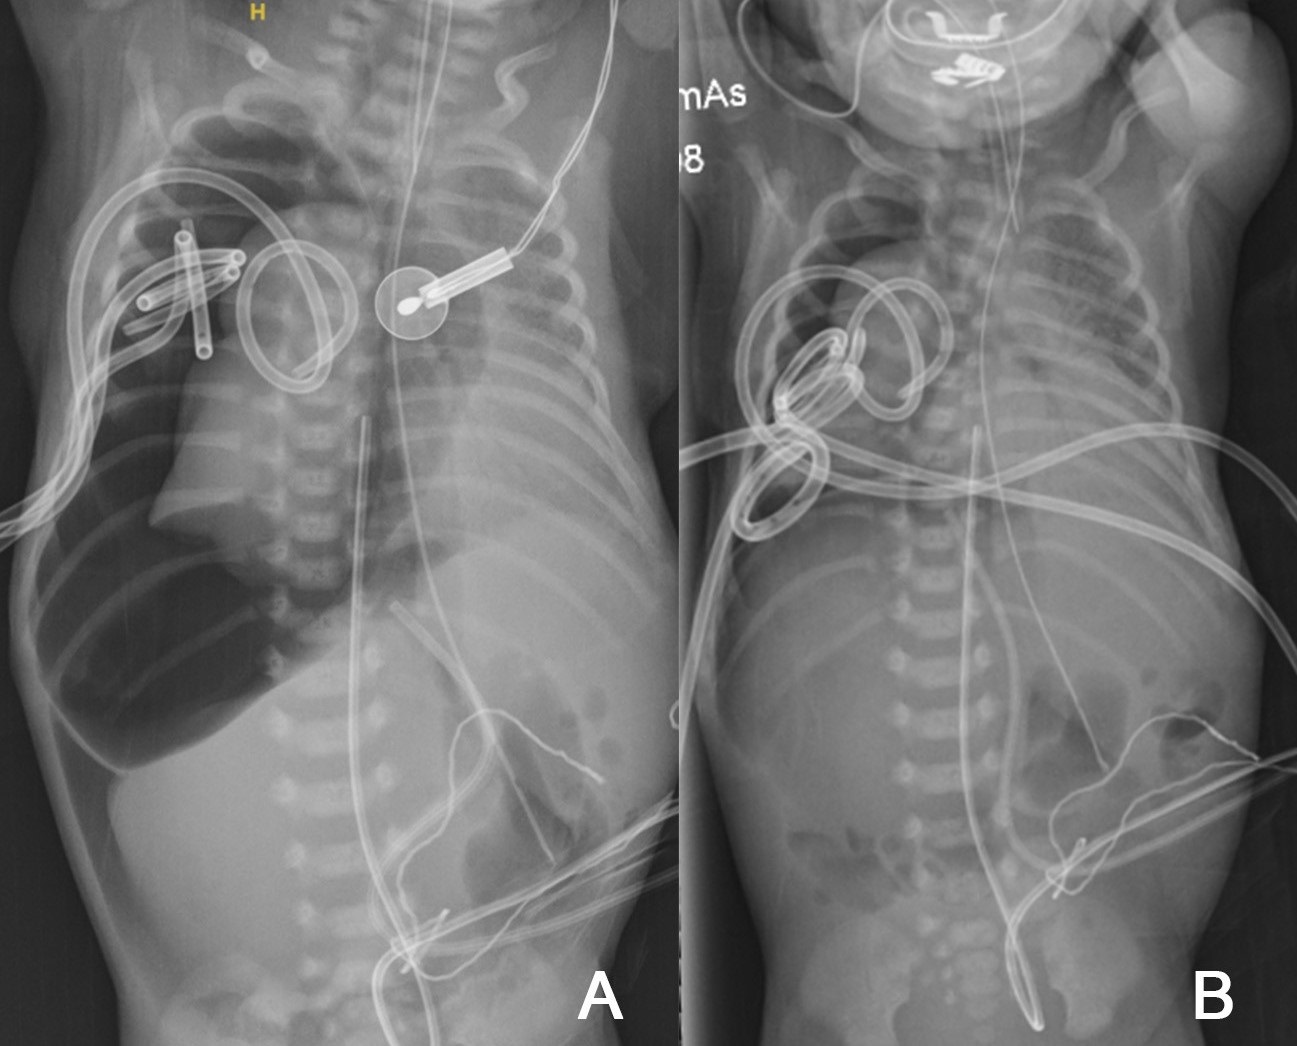

An iatrogenic tracheobronchial injury was suspected. On day 2, he developed a greater oxygen requirement; transillumination and radiography confirmed persistent pneumothorax, this time with pneumomediastinum and pneumoperitoneum, requiring a third chest drain. He was then transferred to the regional pediatric center. After a fourth TT (Fig. 2B) due to a massive ongoing air leak (Fig. 2A), high-frequency oscillatory flow ventilation (HFOV) was tried.

Chest and abdominal radiographs showing right-sided pneumothorax, pneumomediastinum, and pneumoperitoneum (massive air leak)– before (A) and after (B) drain 4.